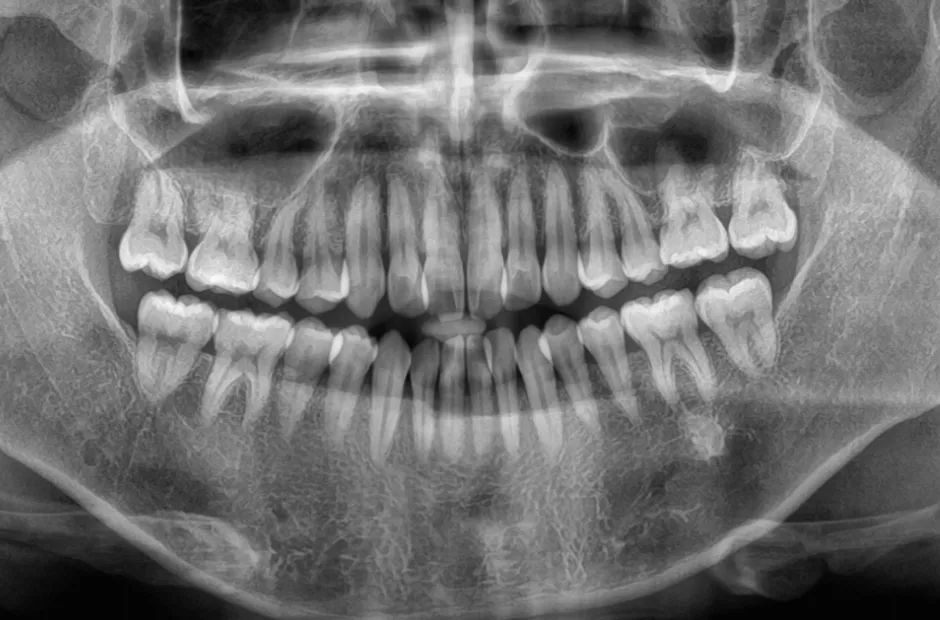

過剰歯

| 診断名・主訴 | でこぼこ |

|---|---|

| 年齢・性別 | 22歳・女性 |

| 治療期間・回数 | 1年6か月 |

| 治療に用いた主な装置 | リンガルブラケット |

| 抜歯部位 | 過剰歯 |

| 治療費 | 100万円(税抜) |

| リスク・副作用 | 装置による違和感・疼痛・歯肉退縮・歯根吸収・虫歯のリスクなど |